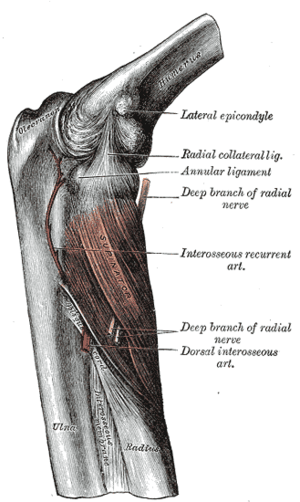

Left: anterior and ulnar collateral ligaments

Right: posterior and radial collateral ligaments

The elbow, like other joints, has ligaments on either side. These are triangular bands which blend with the joint capsule. They are positioned so that they always lie across the transverse joint axis and are, therefore, always relatively tense and impose strict limitations on abduction, adduction, and axial rotation at the elbow.[7]

The ulnar collateral ligament has its apex on the medial epicondyle. Its anterior band stretches from the anterior side of the medial epicondyle to the medial edge of the coronoid process, while the posterior band stretches from posterior side of the medial epicondyle to the medial side of the olecranon. These two bands are separated by a thinner intermediate part and their distal attachments are united by a transverse band below which the synovial membrane protrudes during joint movements. The anterior band is closely associated with the tendon of the superficial flexor muscles of the forearm, even being the origin of flexor digitorum superficialis. The ulnar nerve crosses the intermediate part as it enters the forearm.[7]

The radial collateral ligament is attached to the lateral epicondyle below the common extensor tendon. Less distinct than the ulnar collateral ligament, this ligament blends with the annular ligament of the radius and its margins are attached near the radial notch of the ulna.[7]